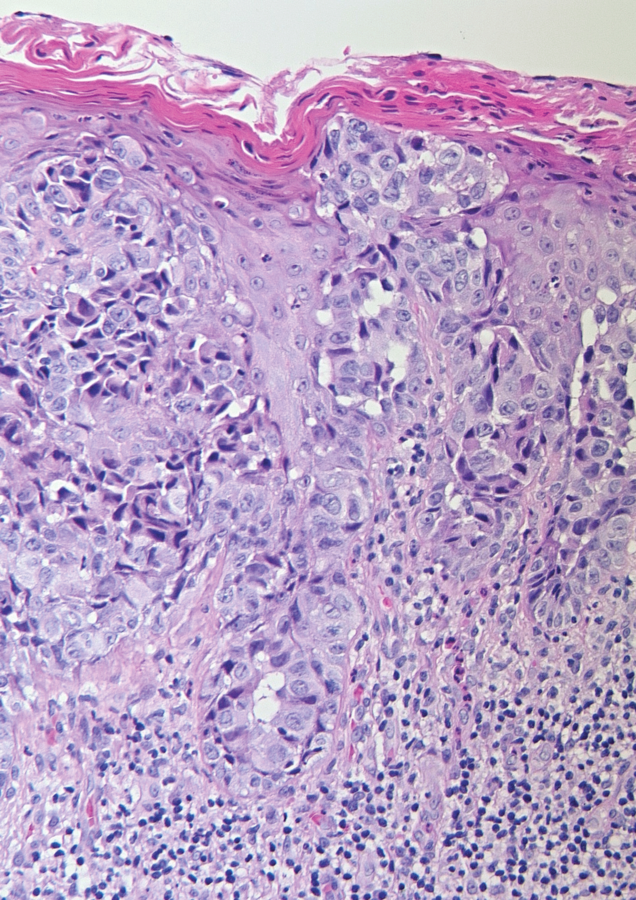

Große Krebszellen mit atypischen Kernen ziehen sich durchs gesamte Epithel. Große Krebszellen mit atypischen Kernen ziehen sich durchs gesamte Epithel. © Sorhage B. Wehrmed Monatsschr 2019; 63: 313-316 © Beta Verlag & Marketinggesellschaft mbH, Bonn